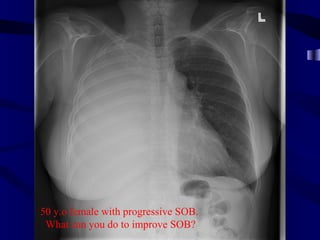

50 y.o femalewith progressive SOB. What can you do to improve SOB?

Volume loss withatelectasis Mass effect with large effusion